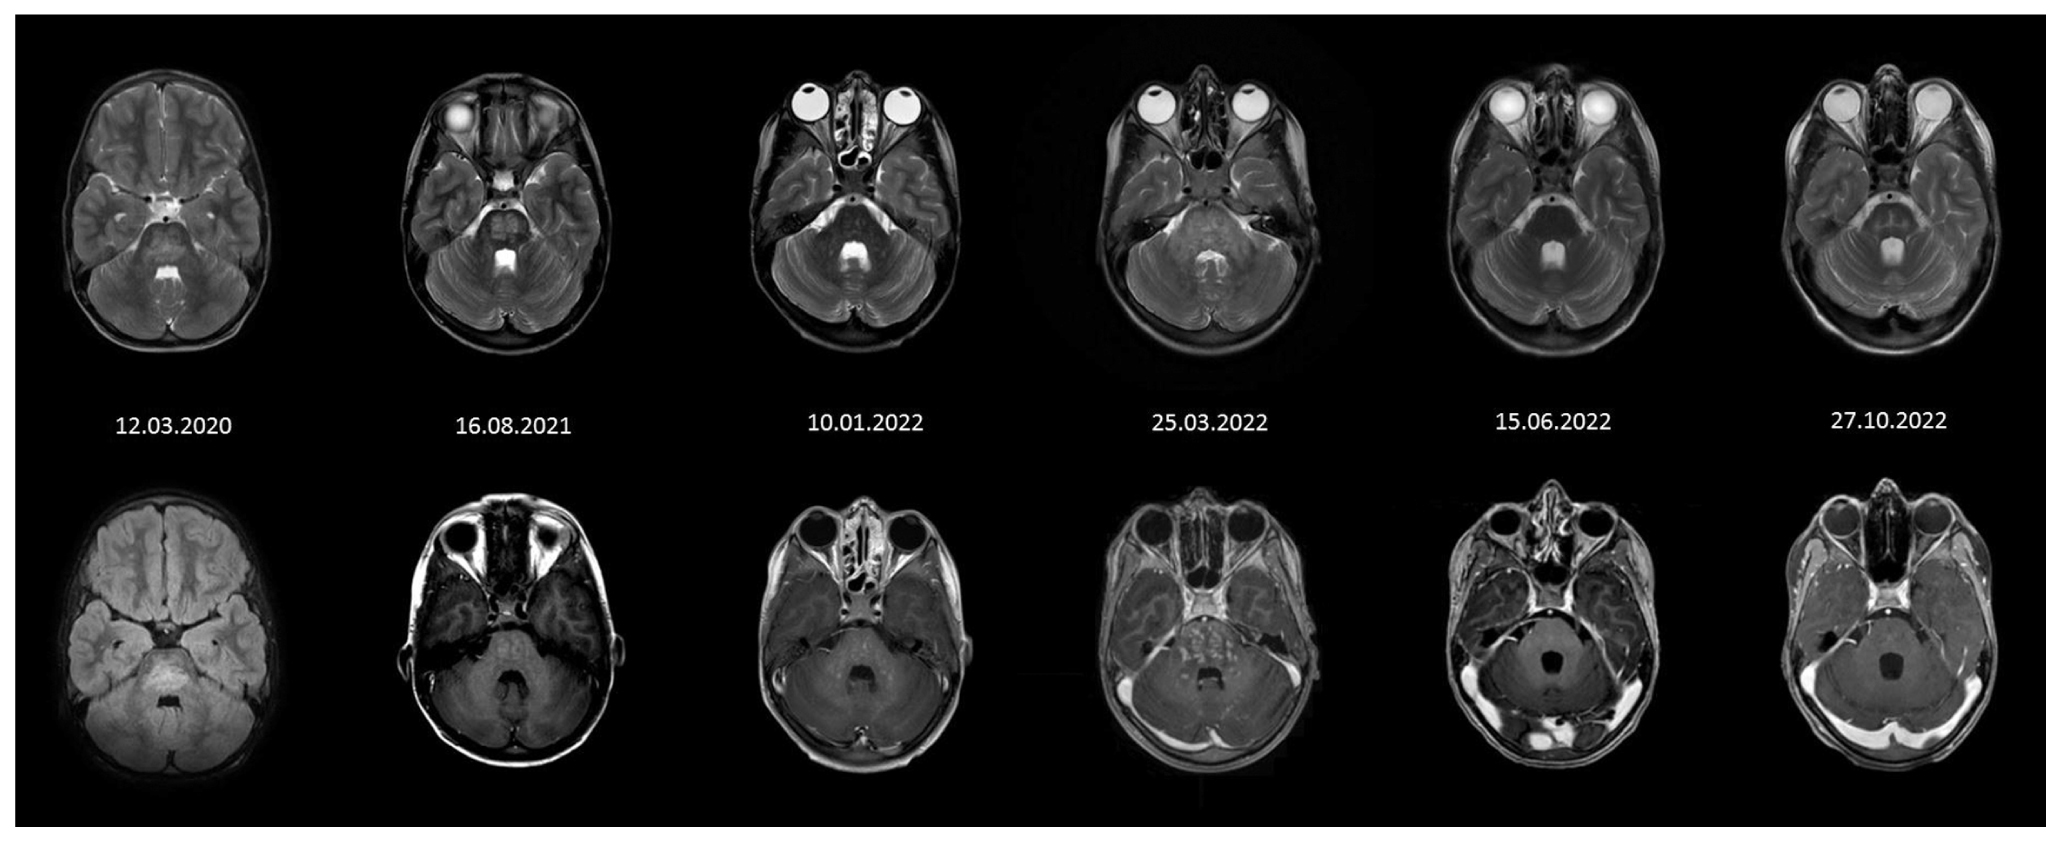

Общепринятых рекомендаций по длительности проводимой терапии на данный момент не существует [12]. По данным исследований, риск рецидива при приеме кортикостероидов в дозе более 20 мг/сут минимальный, но изучаются также альтернативные варианты лечения [12]. В нашем наблюдении прекращение приема кортикостероидов спровоцировало у пациента развитие рецидива. После последней пульс-терапии ребенку был назначен курс поддерживающей терапии метилпреднизолоном, на фоне которого отмечались клиническое улучшение и регресс МР-изменений головного мозга (рис. 7).

Рис. 7. Фрагменты исследований МРТ, полученные в порядке их выполнения и позволяющие наглядно оценить динамику изменений. / Fig. 7. Fragments of MRI studies obtained in the order they were performed that allow one to clearly assess the dynamics of changes.